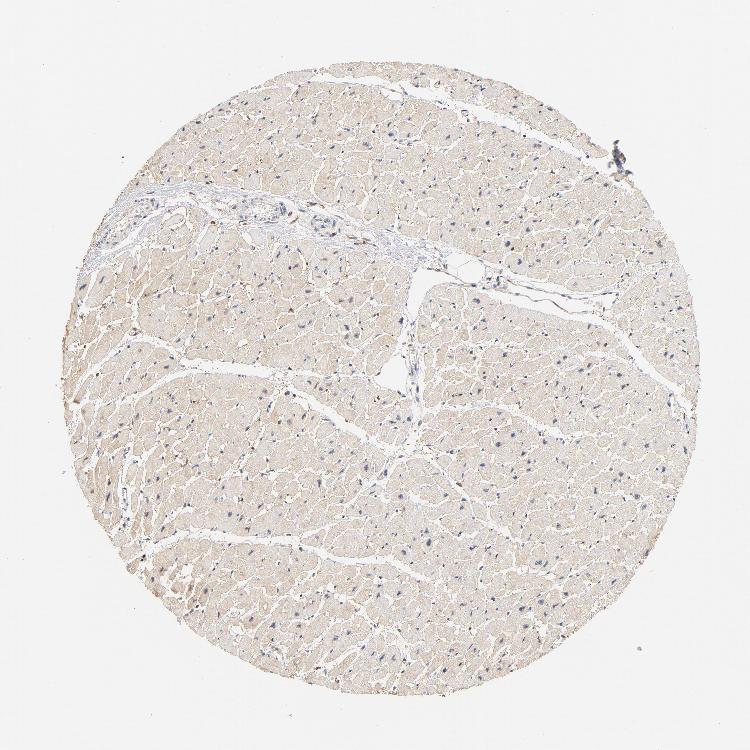

HEART MUSCLE - Antibody stainingi

Antibody staining in the annotated cell types in the current human tissue is reported as not detected, low, medium, or high, based on conventional immunohistochemistry profiling in selected tissues. This score is based on the combination of the staining intensity and fraction of stained cells.

Each image is clickable and will lead to virtual microscopy that enables deeper exploration of all samples and also displays staining intensity scores, fraction scores and subcellular localization as well as patient and tissue information for each sample.

Antibody HPA021616Antibody CAB004035Antibody CAB047324Antibody CAB075739

Cardiomyocytes Not detectedNot detectedLowNot detected